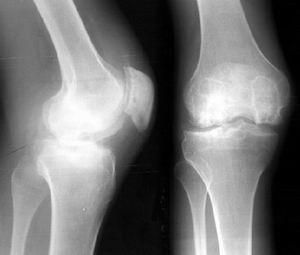

X線檢查

骨刺X線平片不僅為骨質增生的常規檢查方法,有的學者還認為骨質增生的X線檢查是追蹤病情變化的金標準。

拍膝關節片時,病人應取站立位拍前後位和側位片,髖關節和手關節可只拍前後位片。在早期階段,X線片大多正常,中晚期可見關節間隙不對稱性狹窄、關節面下骨硬化和變形、關節邊緣骨贅形成,關節面下囊腫和關節腔游離液體等。

骨質增生的x線特點為:關節面硬化變形;關節鼠;關節邊緣骨贅;關節間隙狹窄,如在膝關節,可小於3毫米;軟骨下囊性變,其邊緣分界清楚;骨變形或關節半脫位。

3、膝關節骨質增生的症狀

臨床表現:初期,起病緩慢者膝關節疼痛不嚴重,有可持續性隱痛,氣溫降低時疼痛加重,與氣候變化有關,晨起後開始活動,長時間行走,劇烈運動或久坐起立開始走時膝關節疼痛僵硬,稍活動後好轉,上、下樓困難,下樓時膝關節發軟,易摔倒。蹲起時疼痛,僵硬,嚴重時,關節酸痛脹痛,跛行走,合併風濕病者關節紅腫,畸形,功能受限,伸屈活動有彈響聲,部分患者可見關節積液,局部有明顯腫脹、壓縮現象。